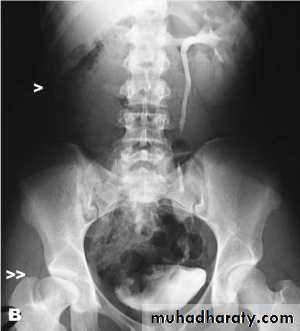

IVU shows :

The kidneys at low position .

Close to the spine with long axis parallel to the spine .

Mal–rotation manifested by medially directed calyces.

The renal pelvis and ureters are anterior and lateral in position .

HORSE –SHOE KIDNEY

HORSE SHOE KIDNEY